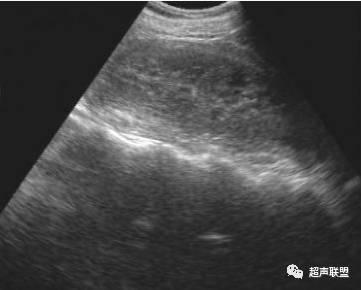

右肾挫伤,肾盂积血 - 超声医学讨论版 - 爱爱医医学论坛

图片尺寸768x576